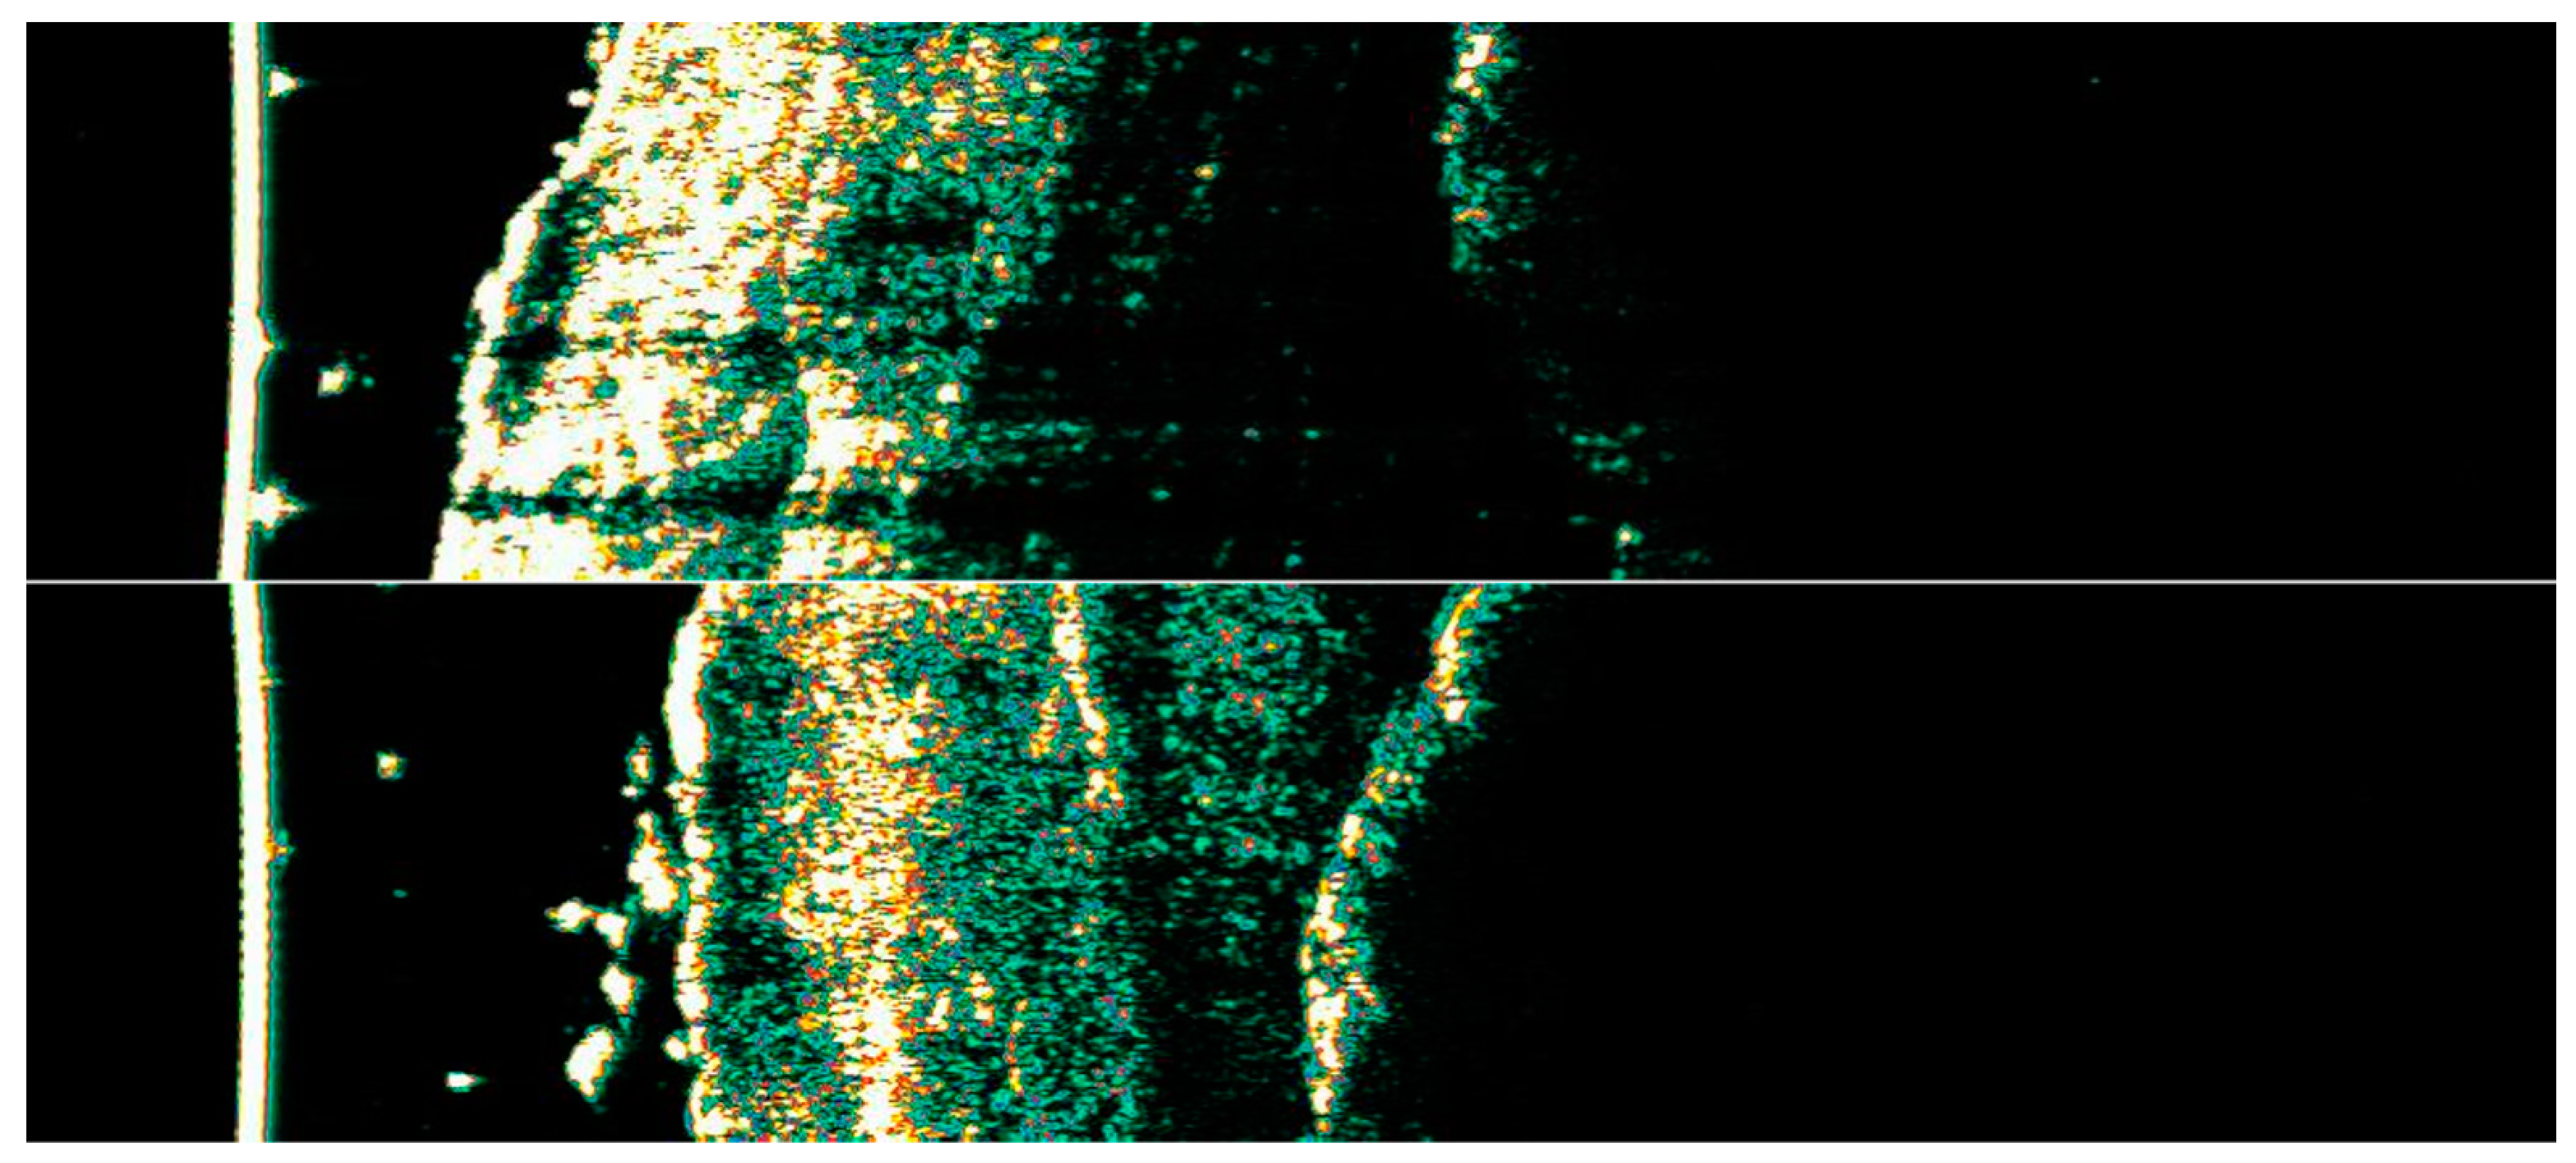

3.1. Clinical and Dermoscopic Involution of HIFU-Treated Basal Cell Carcinoma